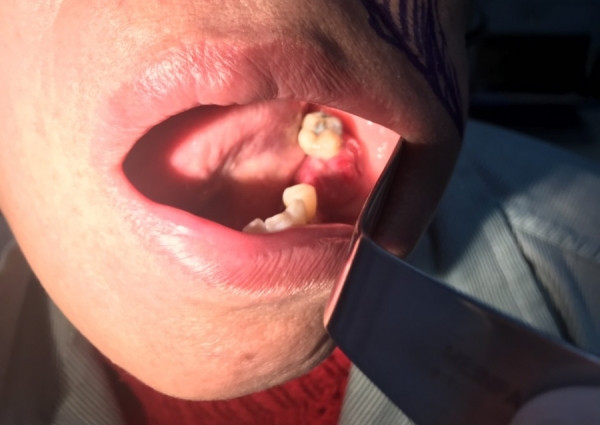

Bệnh nhân bị ung thư lợi đã di căn nhưng triệu chứng chỉ như bị viêm răng lợi

Đến khi thấy lợi sưng to dần, chảy máu, ăn uống khó khăn, bà B. mới đến Bệnh viện Ung Bướu Hà Nội để kiểm tra. Tại đây, các bác sĩ phát hiện bệnh nhân có khối ung thư lợi đã ăn vào xương hàm dưới, tiến triển đến giai đoạn 4, chỉ định phẫu thuật cắt khối ung thư lợi hàm dưới triệt căn có tạo hình một thì.